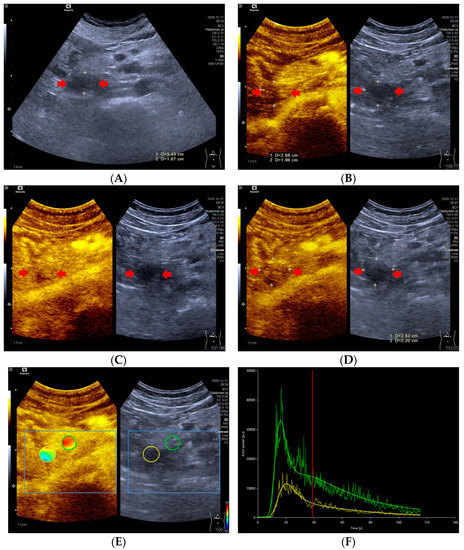

Significant differences in TIC shape (p < 0.05) were observed between pNETs G1/G2 and pNETs G3/pNECs. In the group of pNETs G1/G2, 22 (22/31, 70.79%) TICs were persistently above or equal to TICs of pancreatic parenchyma from the arterial phase to the late phase. Five TICs of pNETs G1/G2 were above those of pancreatic parenchyma in the arterial phase, but below the TICs of pancreatic parenchyma in the venous phase or late phase due to the rapid wash-out of contrast agent [Figure 1]. On the contrary, seven cases (7/11, 63.64%) of pNETs G3/pNECs had TICs below those of pancreatic parenchyma consistently after injecting contrast agent [Figure 2].

Figure 1.

A 59-year-old female with a pNETs G1 lesion (Ki 67 proliferation index of 2%). The pNETs lesion located in pancreatic head was hypoechoic (A) with abundant internal color doppler flow imaging signal (B). After injecting the contrast agent, pNETs lesion showed hyperenhancement in the arterial phase (C) and isoenhancement in the venous phase (D). The pNET’s microvascularization was assessed using VueBox®, an external perfusion software. Regions of interest of the pNETs lesion (yellow circle) and surrounding pancreatic parenchyma (green circle) were placed manually (E). The time intensity curve revealed that in the arterial phase, the yellow curve (pNETs lesion) was higher than the green curve (pancreatic parenchyma), and in the venous phase and late phase, the two curves almost completely overlapped (F).